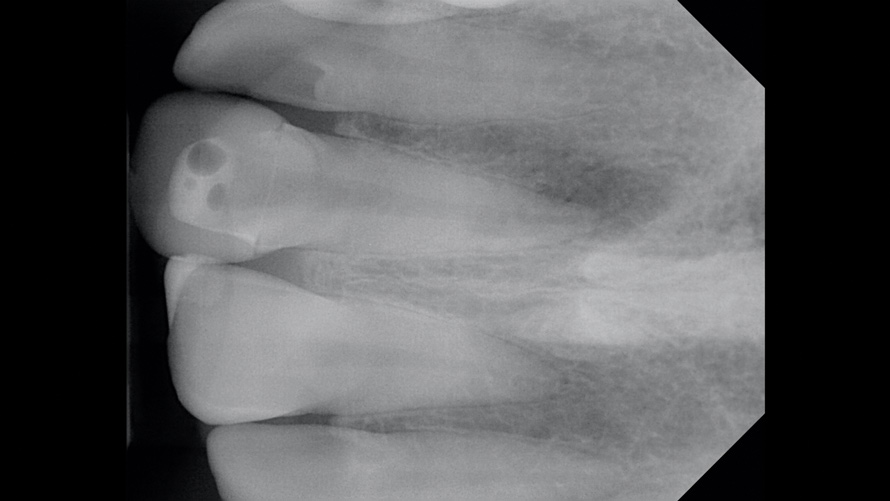

In the first case, the patient reported a history that included childhood dental trauma without swelling or discomfort. The intraoral examination indicated that the existing all-ceramic restoration on tooth No. 8 possessed an inappropriate morphology, surface topography, and shade. Radiographically, tooth No. 8 exhibited a large underlying resin core with significant porosity and periapical radiolucency (Figure 3). The diagnosis for tooth No. 8 was pulp necrosis with asymptomatic apical periodontitis.

(3.) Case 1: Preoperative radiograph of the maxillary right central incisor, demonstrating periapical radiolucency and porous core buildup.

Figure 3